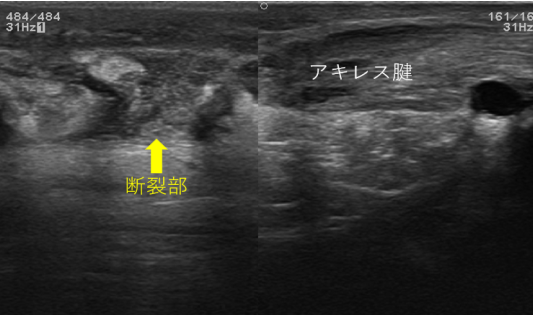

スポーツなどでみられるアキレス腱断裂。以前は手術が主流の時代もありましたが最近では保存療法(手術をしない治療)でも良好な結果が得られることがわかってきているため手術をしないことが多くなってきています。

44歳・女性:フットサルをしていた時に急にアキレス腱部分を後ろから蹴られた感じがして受傷し来院された患者様です。

この方は歩行可能でしたがアキレス腱部が完全に陥凹しているためアキレス腱断裂と判断しました。

アキレス腱断裂専用の装具は時期に応じて足関節の角度を調整可能であり、エコー観察を行いながら患部の状態を確認して関節可動域訓練や筋力訓練などを行っていき、約半年で軽いランニング程度まで可能となります。

正常のアキレス腱

アキレス腱断裂